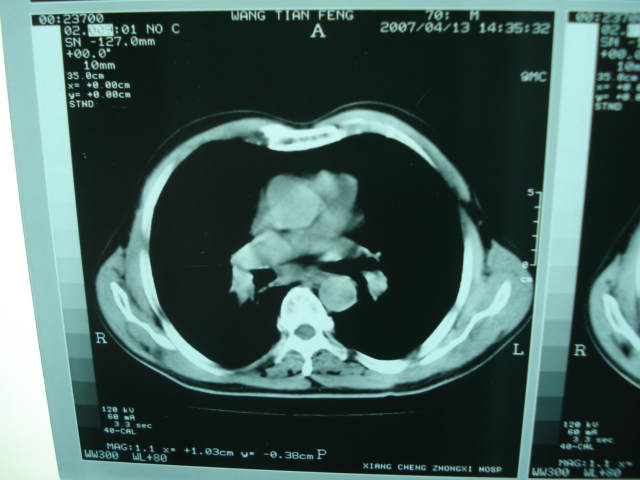

以下是引用狙击手在2007-4-18 20:17:00的发言:[br]原:2007/1/22号ct片:右肺上叶可见片状、云雾状高密度影,右肺上叶后段可见三角形高密度影,尖端指向肺门,右肺上叶后段支气管壁不规则增厚,管腔不规则增厚,纵隔未见肿大淋巴结.[br] 今ct:右肺上叶片状影增大,右肺上叶后段不张及右肺上叶后段支气管壁不规则增厚未见变化,右肺下叶背段支气管壁不规则增厚.[br] 如果考虑肺结核,但从临床证据看竟然没有一项支持肺结核,不知患者是否已经过正规抗结核治疗。没有的话,3个月了前后片看起来变化不大,似乎有不太符合肿瘤征象,不知患者是否抗炎治疗过,下叶支气管增粗还是要高度警惕,同意楼主意见,将常规病理,生化检查再做一遍。[br]

以下是引用狙击手在2007-4-18 20:17:00的发言:[br]原:2007/1/22号ct片:右肺上叶可见片状、云雾状高密度影,右肺上叶后段可见三角形高密度影,尖端指向肺门,右肺上叶后段支气管壁不规则增厚,管腔不规则增厚,纵隔未见肿大淋巴结.[br] 今ct:右肺上叶片状影增大,右肺上叶后段不张及右肺上叶后段支气管壁不规则增厚未见变化,右肺下叶背段支气管壁不规则增厚.[br] 如果考虑肺结核,但从临床证据看竟然没有一项支持肺结核,不知患者是否已经过正规抗结核治疗。没有的话,3个月了前后片看起来变化不大,似乎有不太符合肿瘤征象,不知患者是否抗炎治疗过,下叶支气管增粗还是要高度警惕,同意楼主意见,将常规病理,生化检查在做一遍。[br]